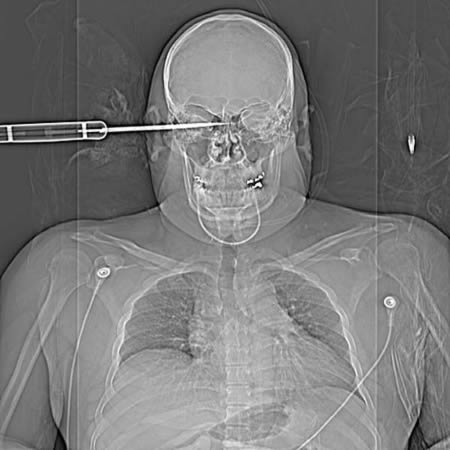

Մահացու վերքերից փրկվածների անհավանական պատմությունները

7. 23-ամյա տղամարդը ողջ էր մնացել այն բանից հետո, երբ դաշույնը մխրճվել էր նրա աչքի մեջ: Բույ Նգոկ Տուանը հարված էր ստացել 50 սմ-ոց դաշույնով տաքսու վարորդի կողմից: Վերքը մոտ 10 սմ խորության էր: